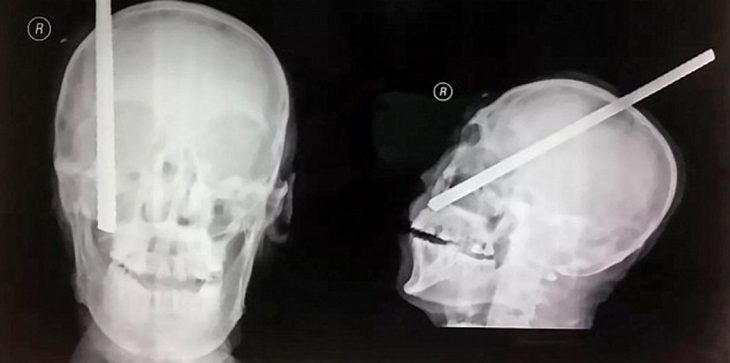

بالصور.. نجاة عامل بناء اخترق سيخ حديدي رأسه